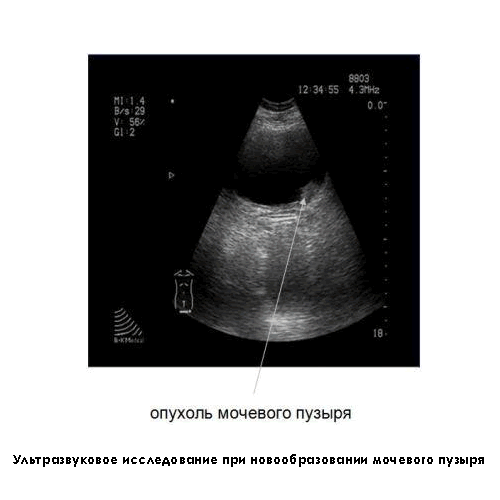

Прежде чем начать лечение рака мочевого пузыря, следует точно диагностировать заболевание. Существует несколько способов диагностирования онкологии:

- УЗИ (ультразвуковая диагностика);